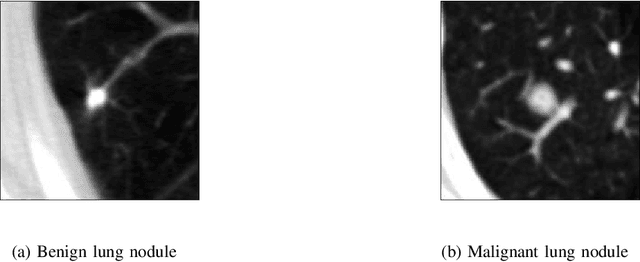

Abstract:Quantum machine learning is receiving significant attention currently, but its usefulness in comparison to classical machine learning techniques for practical applications remains unclear. However, there are indications that certain quantum machine learning algorithms might result in improved training capabilities with respect to their classical counterparts -- which might be particularly beneficial in situations with little training data available. Such situations naturally arise in medical classification tasks. Within this paper, different hybrid quantum-classical convolutional neural networks (QCCNN) with varying quantum circuit designs and encoding techniques are proposed. They are applied to two- and three-dimensional medical imaging data, e.g. featuring different, potentially malign, lesions in computed tomography scans. The performance of these QCCNNs is already similar to the one of their classical counterparts -- therefore encouraging further studies towards the direction of applying these algorithms within medical imaging tasks.